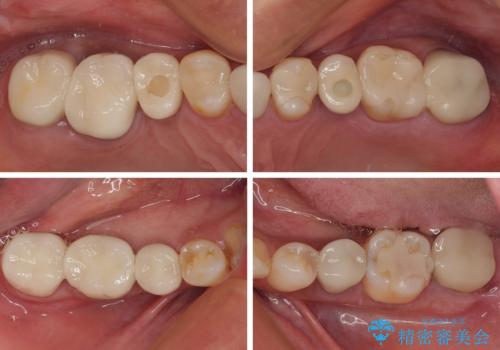

- 地元の歯科医院で治療を行っていたものの、難しいので都会に行くように指示をされたとのことで来院された患者様です。

右下のむし歯が歯肉縁下に及んでおり、歯周外科処置(歯冠長延長術)を行った上で、根管治療を行い、状態を整えて補綴治療を行うこととしました。

新幹線で通院をされていたため、極力診療回数を減らして、一度にまとめて多くの処置を行うことで負担を軽減しました。